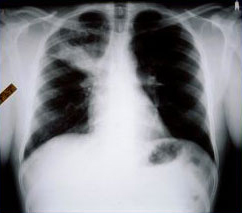

Aspergilose broncopulmonar alérgica

Radiografia torácica em um paciente com aspergilose broncopulmonar alérgica (ABPA): o padrão clássico de "dedo de luva" representa as vias aéreas bronquiectásicas centrais impactadas com muco

Do American College of Chest Physicians, PCCU Volume 17, Lesson 17: Allergic bronchopulmonary aspergillosis; usado com permissão